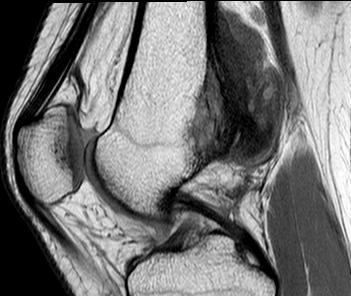

MRI

Parosteal osteosarcoma posterior distal femur

Parosteal osteosarcoma anterior tibia

Parosteal osteosarcoma posterior tibia